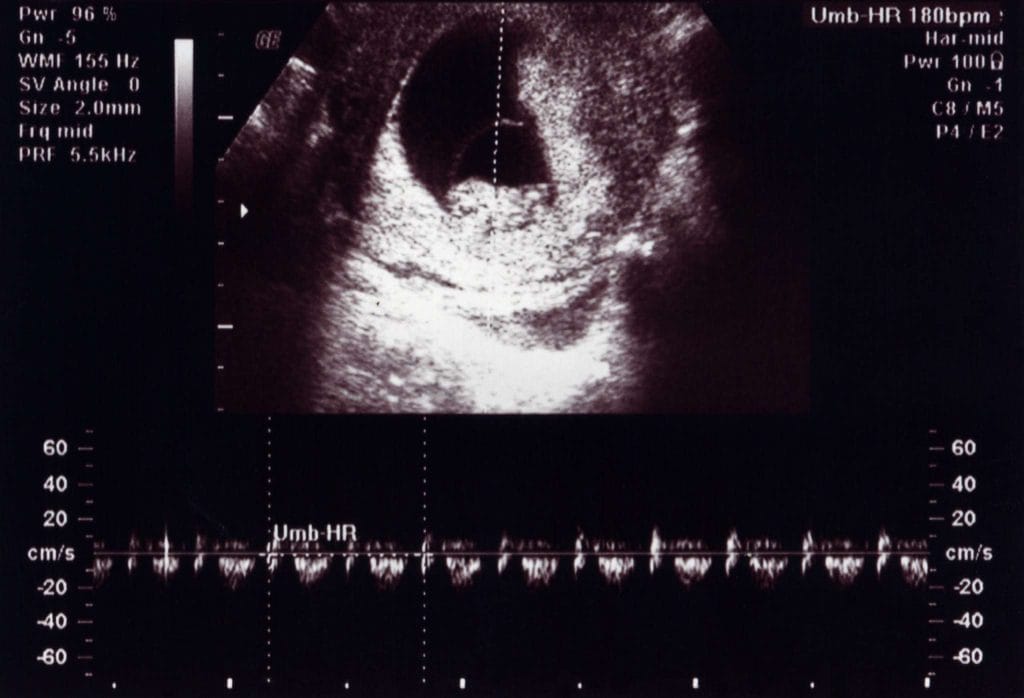

10 Haftalık Bebek Ultrason Görüntüsü Nasıldır?

- haftada ultrason, gebeliğin sağlıklı ilerleyip ilerlemediğinin değerlendirilmesi açısından çok kıymetlidir. Bu dönemde yapılan ultrasonografi genellikle vajinal yolla (transvajinal) ya da karından (abdominal) yapılabilir. Özellikle anne adayı zayıfsa ve rahim önde yer alıyorsa karından ultrasonla da net görüntüler elde edilebilir.

Ultrasonda Neler Görülür?

- haftada ultrason sırasında bebeğin artık bir embriyodan çok, minyatür bir insan formuna benzemeye başladığı görülür. Görülebilen yapılar şunlardır:

| Kalp atımı | Dakikada 160-180 arası atım hızıyla görülür ve duyulur. |

Ultrason süresi genellikle 5–10 dakika arasıdır. İşlem sırasında kalp atışları genellikle sesli olarak da dinletilir, bu an birçok anne-baba için duygusal bir dönüm noktasıdır.